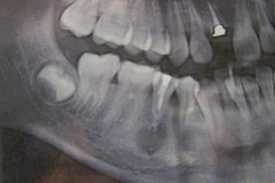

根尖脓肿

主诉:左上后牙疼痛一周余。 病史:左上后牙牙冠缺损一年余未治疗现疼痛明显夜间痛加重故前来就诊